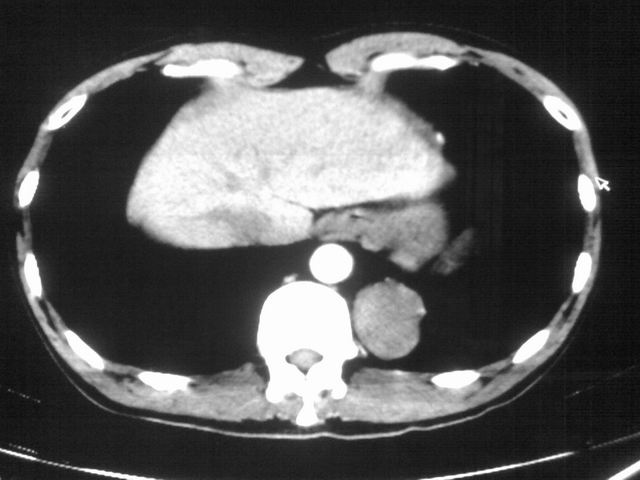

以下是引用苯小孩在2007-4-24 19:46:00的发言:[br]左下肺内侧基底段,见类圆形病灶,边缘清晰光滑.强化后轻中度强化.<平扫第4层面似有从腹主动脉相连血管影,可惜强化扫描这层没有抓住>考虑:左下肺隔离症.建议dsa或薄层强化重建观察.

以下是引用同在2007-4-24 20:11:00的发言:[br]考虑肺隔离症